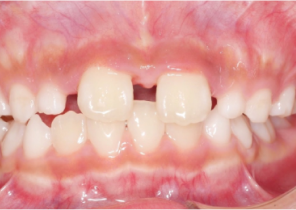

10 năm 0 tháng tuổi, 18 bước nong của Nong hàm khẩu cái Invisalign®

Hàm được nong sau khi sử dụng nong hàm khẩu cái Invisalign®

Sau khi điều trị bằng Invisalign First